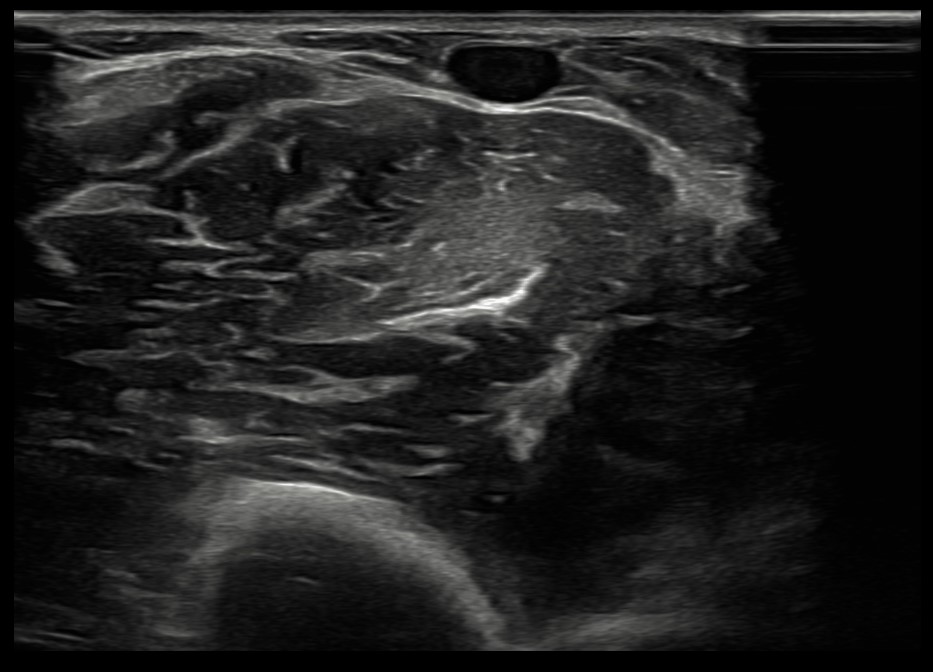

La venopunción ecoguiada se muestra como una técnica segura que ayuda a fomentar medidas de prevención cuaternaria y mejora el control emocional de los pacientes. Actualmente esta técnica se encuentra casi exclusivamente ligada a servicios como urgencias hospitalarias o UCI. Su implementación dentro de la Atención Primaria supone un proceso novedoso y destacable. Hoy en día, las enfermeras especialistas en Familiar y Comunitaria no cuentan en su periodo de residencia con una formación adecuada en esta técnica, por lo que el modelo de formación de formadores y su posterior integración en el EAP se plantea como un proceso innovador y pionero en Atención Primaria del Servicio de Salud del Principado de Asturias. Para iniciar la implementación de esta técnica, se ha realizado formación teórica y práctica conjunta entre residentes de medicina y enfermería.

La venopunción ecoguiada se muestra como una técnica asequible y útil en Atención Primaria, especialmente en casos de venopunción dificultosa.